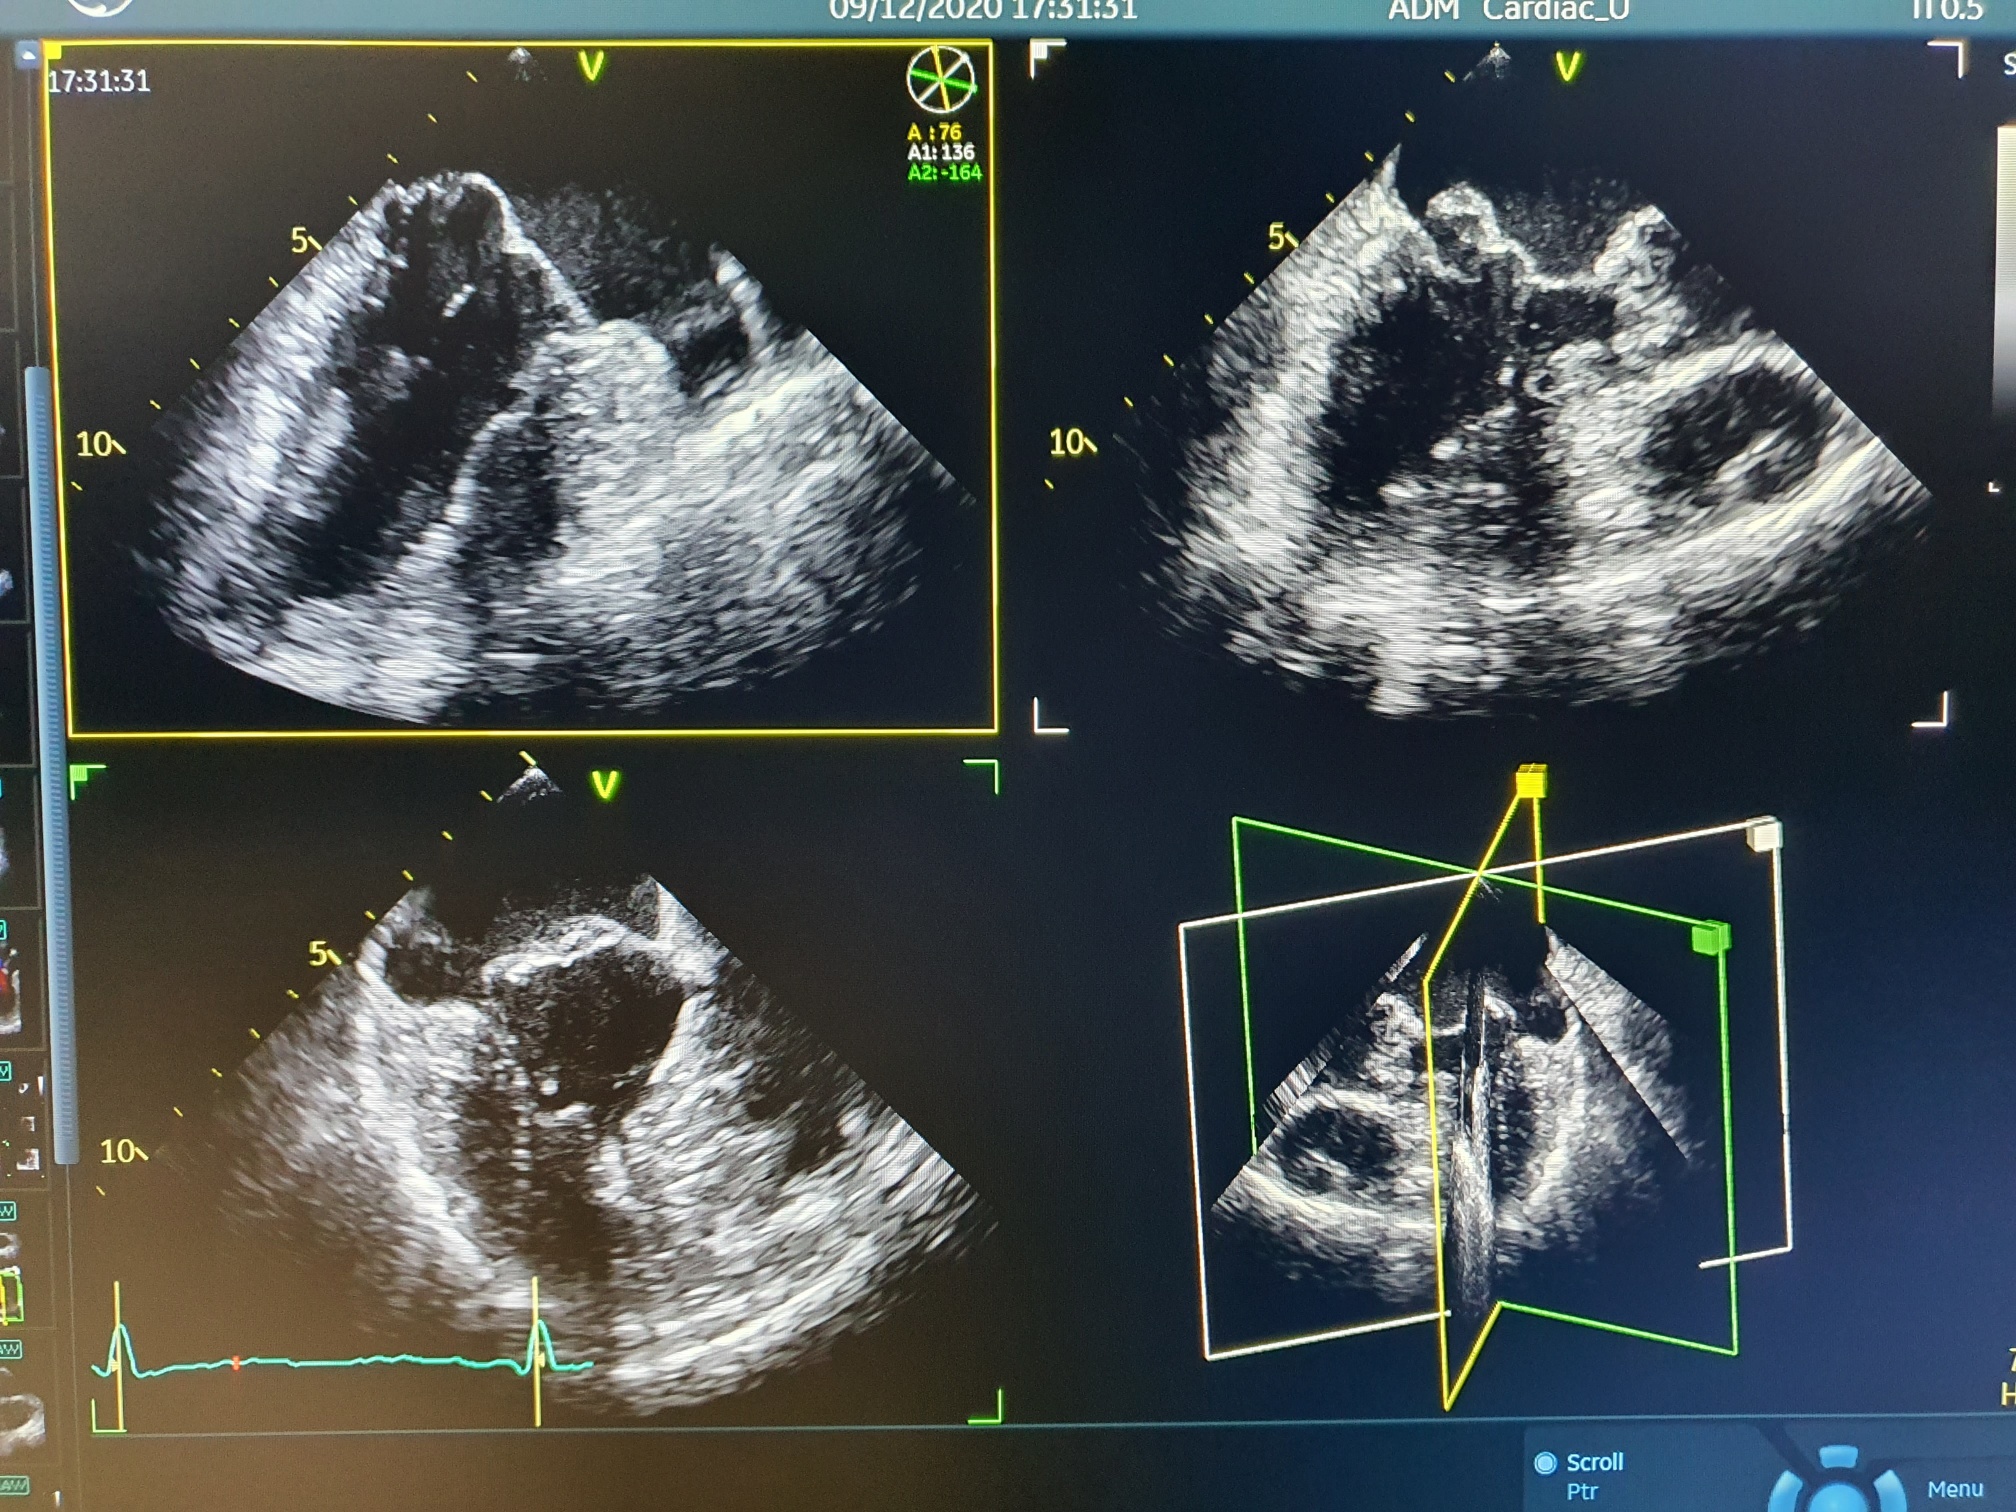

Dzięki dofinansowaniu w wysokości 499 tys. zł, przyznanemu przez marszałka województwa pomorskiego, zespół Oddziału Kardiologicznego otrzymał także nowoczesny echokardiograf Vivid® S7ON GE z najwyższej klasy głowicą przezprzełykową 4D oraz głowicą wewnątrzsercową ICE. Zaawansowany technicznie sprzęt wraz z pełnym oprogramowaniem pozwoli na automatyczną analizę pracy serca, m.in. funkcji skurczowej lewej komory oraz kompleksowej trójwymiarowej oceny aparatu zastawkowego.

– Echokardiograf umożliwia wielopłaszczyznowe obrazowanie wad serca w ramach kwalifikacji do złożonych operacji kardiochirurgicznych oraz inwazyjną ocenę struktur serca w trakcie wykonywania skomplikowanych zabiegów w Pracowni Elektrofizjologii lub Pracowni Hemodynamicznej – wyjaśnia dr Damian Sendrowski.

- Nowoczesny echokardiograf w Oddziale Kardiologicznym. Mat. prasowy WSS w Słupsku